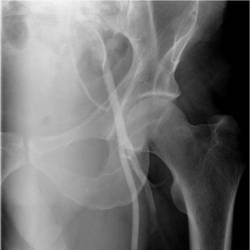

Gallery of Unlabled Radiographs from Lecture (Dr. French) - 2020

Click a thumbnail to enter the gallery display. Click the file name link at the bottom left of the gallery display to view the image at high resolution.